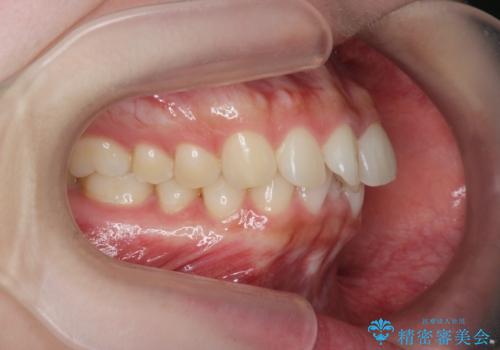

マウスピース 狭窄歯列の改善

- 噛み合わせが深い、笑った時の歯並びの改善を求めて来院されました。

マウスピース型の矯正装置インビザラインを用いた治療を計画します。

狭くなってしまった歯並びを放物線状に並べることで噛み合わせの安定・見た目の改善・ガタつきの改善を達成することができました。